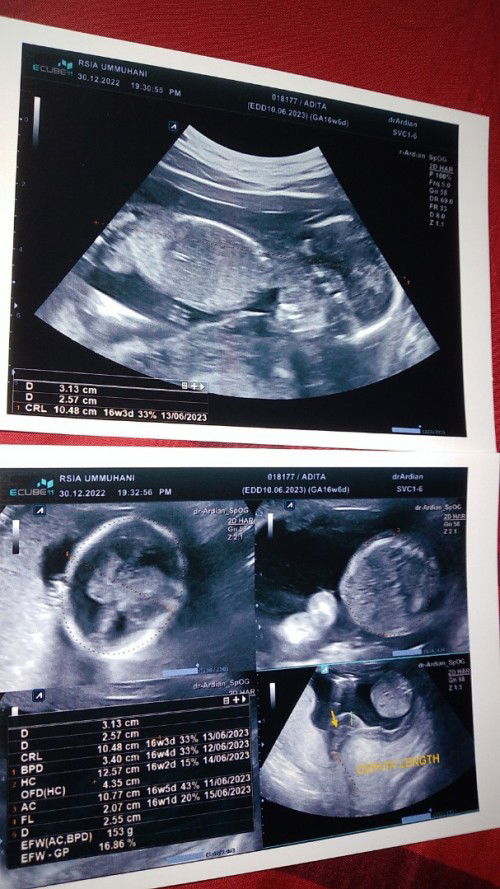

Saya minggu lalu rawat inap karena pendarahan itu di 13w tp hasil usg 14w. Bedrest total di rs. Segala obat masuk lewat infus. Alhamdulillah babies gpp sehat sampe sekarang. Pendarahan jg udah berhenti tp masih disuruh terusin minum microgest dan duphaston.

saya keluar darah dari hamil 13 minggu sampai 15 minggu masuk ugd di usg katanya treathened abortion tapi di lihat dari usg bayi masih ada dan sehat sehat

iya saya rutin periksa, tiap flek darah pasti saya langsung ke dokter, langsung usg. alhamdulillah janin sehat, tapi memang ada gumpalan darah di bawah kantung ketuban jadi harus bedrest